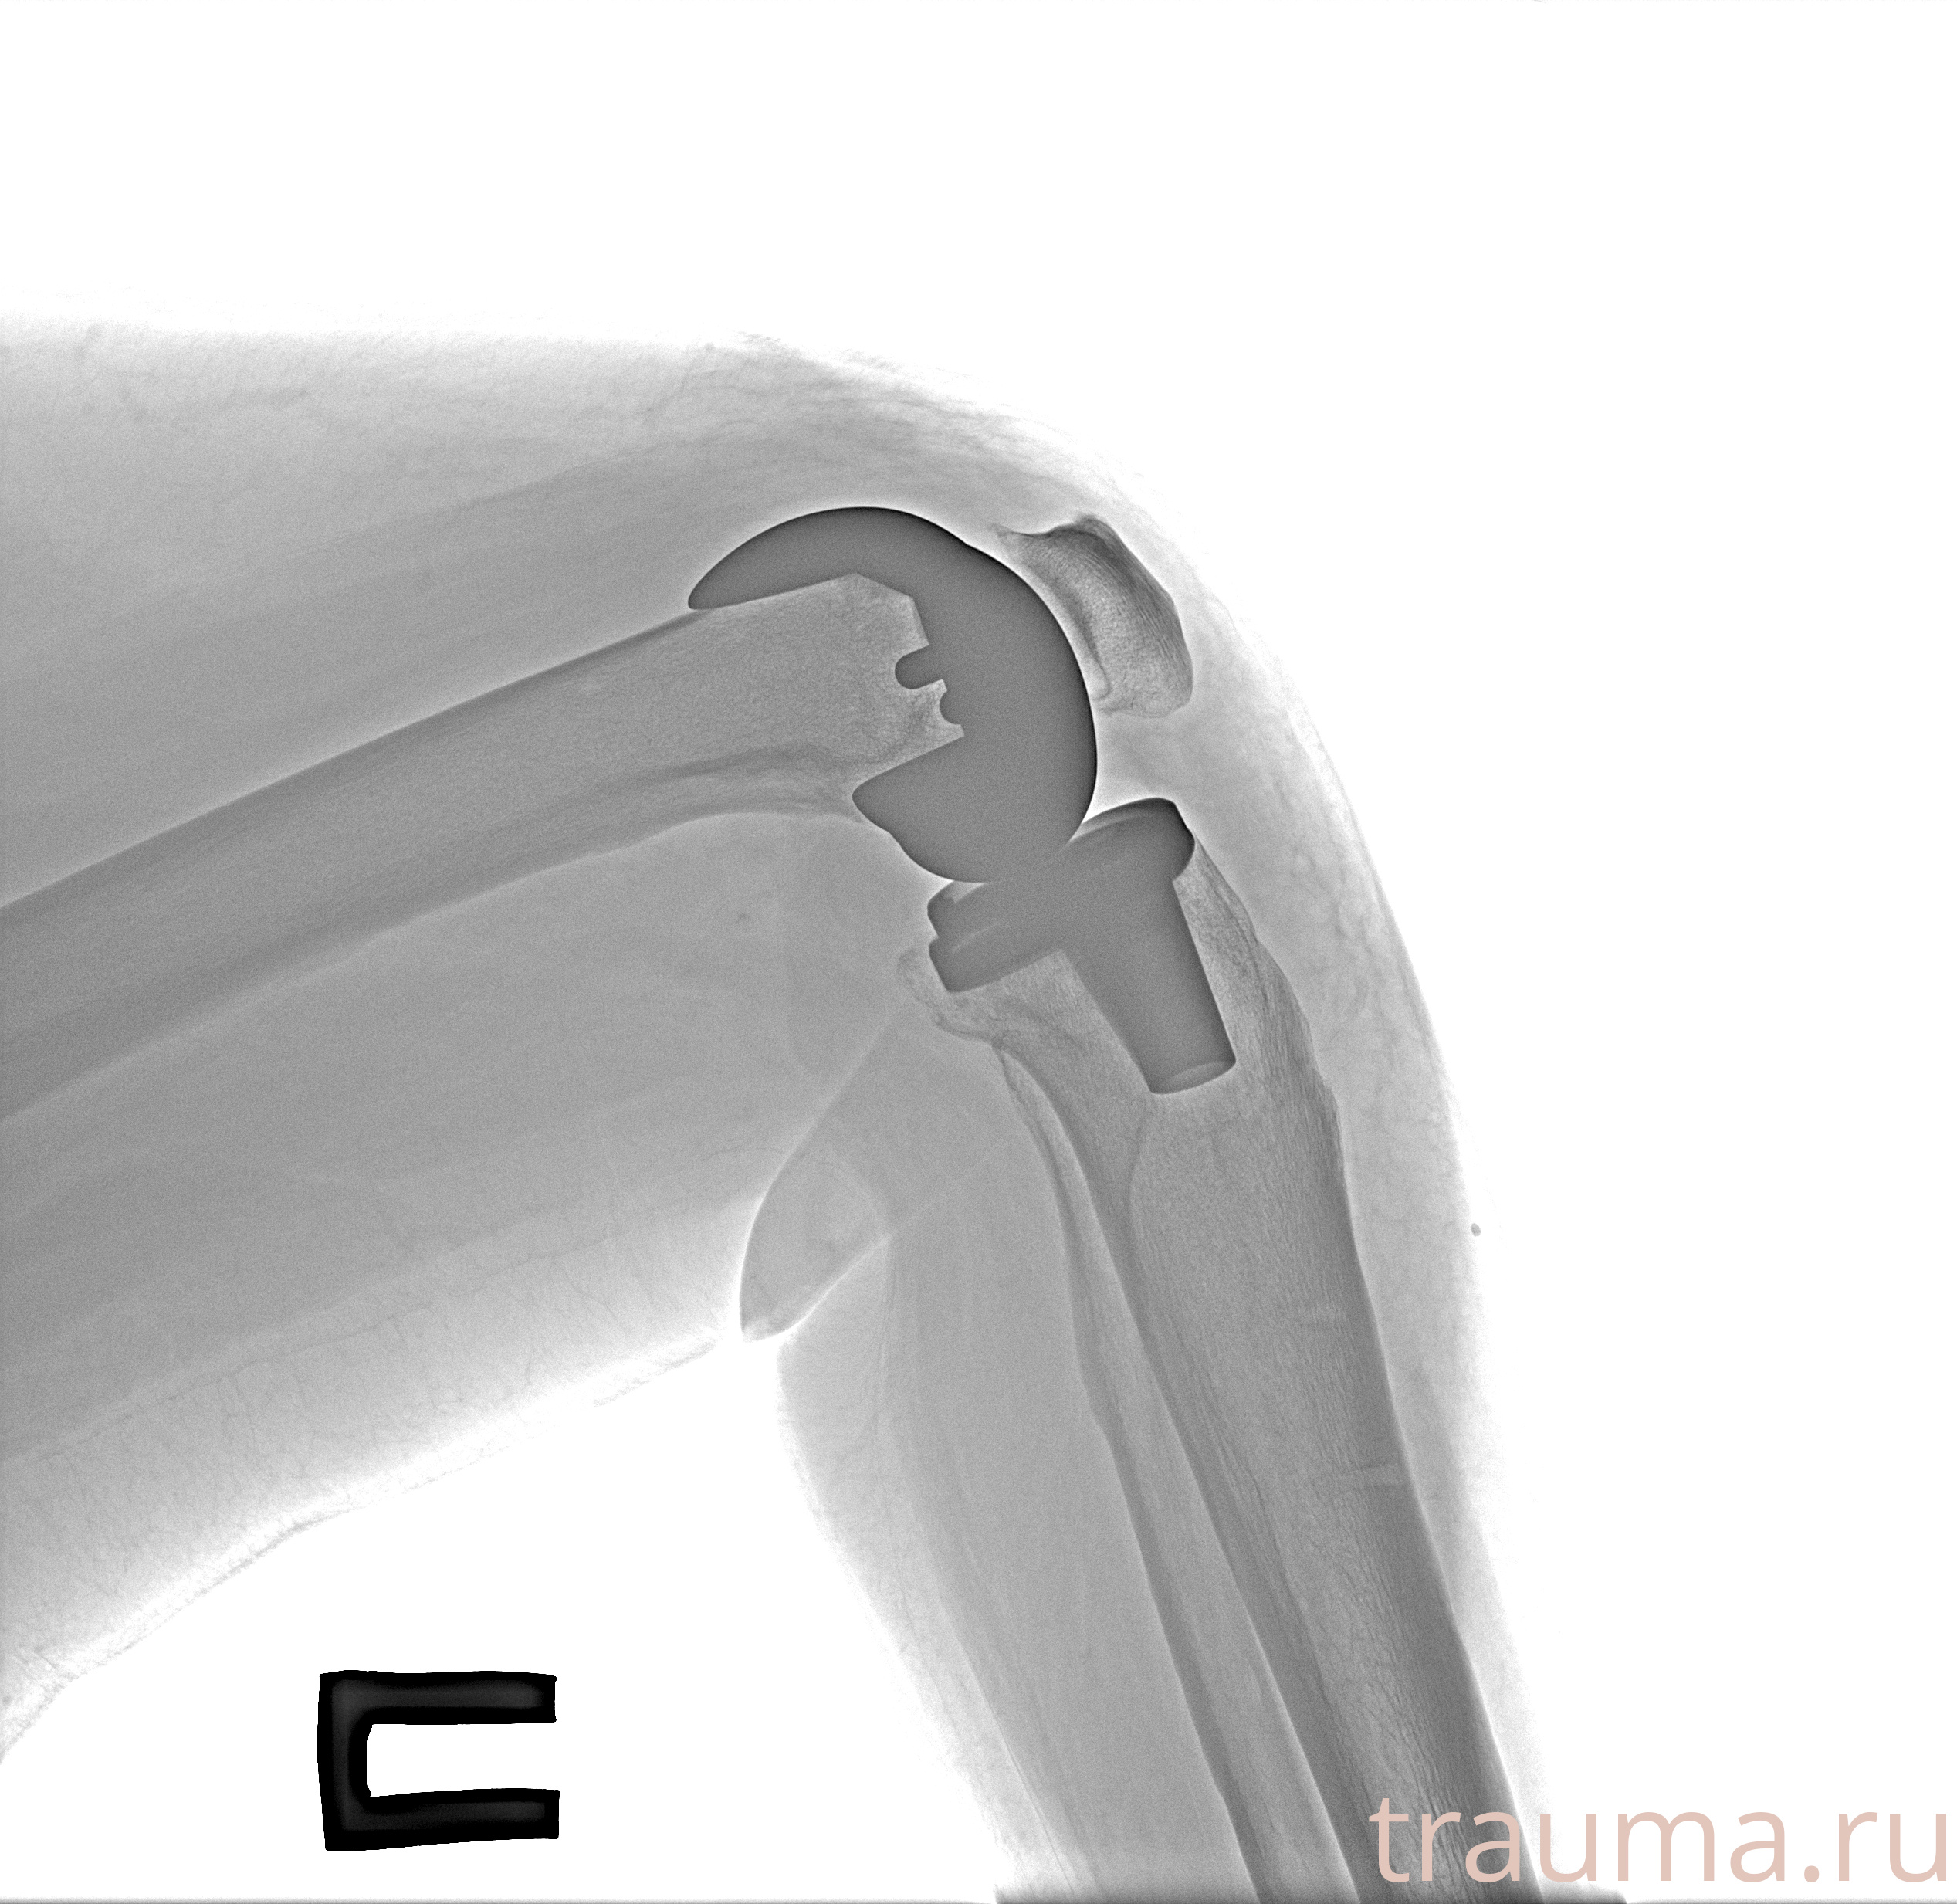

Рентгенограммы

Рентген на дому: по вашему адресу приезжает врач-рентгенолог, травматолог-ортопед с мобильным рентгеновским аппаратом, проводит диагностику травмы или заболевания, делает необходимые рентгенограммы, дает рекомендации по дальнейшему лечению. Получить качественные снимки в домашних условиях возможно благодаря уникальной методике, разработанной МосРентген Центром для института  Склифосовского